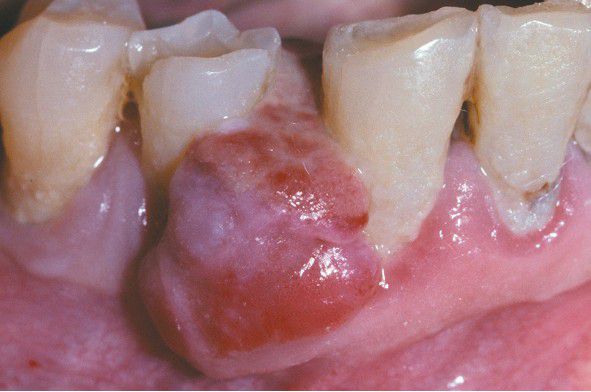

Peripheral Giant Cell Granuloma

. Ulcerated mass of the mandibular gingiva.